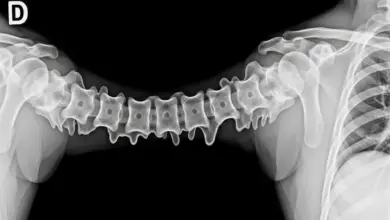

Esta síndrome ocorre quando há compressão do feixe de nervos espinais chamado cauda equina, localizado na parte inferior da coluna vertebral.

A síndrome da cauda equina (SCE) caracteriza-se pela compressão e consequente disfunção das raízes nervosas lombossacrais ao nível do saco dural ou abaixo dele.

Anatomicamente, após o término da medula espinhal no nível da primeira ou segunda vértebra lombar, as raízes nervosas continuam descendo pelo canal medular, formando uma estrutura semelhante a uma cauda de cavalo, daí seu nome.

As consequências da síndrome da cauda equina podem ser devastadoras quando não diagnosticada e tratada rapidamente: o canal vertebral estreita-se gradualmente da região torácica para a região sacral, tornando a cauda equina particularmente suscetível à compressão nessa área.